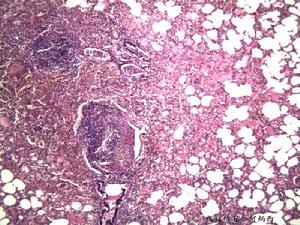

2.其他真菌性變應性呼吸道疾病真菌除可以誘發變應性哮喘外,還可誘發其他肺實質的真菌性支氣管肺的變應性疾病,如真菌誘發的變應性肺炎(又稱真菌性外源性變應性肺泡炎)等,這是一組非IgE介導的真菌性變態反應在肺部的表現,其發病機制、病理生理和臨床過程均與支氣管哮喘有較大區別。作為哮喘防治工作者對這疾病也應有所了解,以便於臨床工作中鑑別診斷和治療。

這些病人常由於吸入生活或職業環境中的各種真菌孢子而致病。有些非真菌性的無機或有機粉塵,化學或藥物等顆粒,吸入後也可致病,但真菌為其主要的病原。該類疾病在臨床上可分為兩類。一類為速髮型,稱急性過敏性肺炎,症狀為在大量吸入致敏真菌後4~8h內出現畏寒、發熱、咳嗽、咳痰、喘憋、乏力、頭痛、肺底有濕性囉音、末梢血白細胞增高等。重者可有肺組織浸潤性病變,肺功能可出現通氣功能不足。二類為隱匿型,亦稱亞急性或慢性過敏性肺炎,是由於長期吸入某種真菌孢子,短期內不出現症狀,日久逐漸出現咳嗽、氣促、乏力、消瘦、活動後氣喘明顯,肺底濕囉音,可有杵狀指,胸部X線出現肺紋理增多,晚期廣泛肺纖維化。肺功能為限制性通氣功能不足,肺組織出現不可逆病變,預後不好。